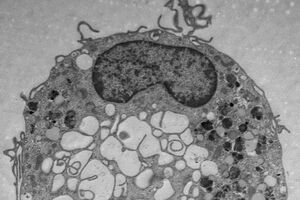

6,8 millions d’euros pour un programme doctoral en immunologie : EURIdoc

Avec EURIdoc, le groupement trinational Eucor élargit son offre pour les doctorants internationaux. Le projet d’Eucor – Le Campus européen visant à mettre en place un nouveau programme doctoral en immunologie a été sélectionné par la Commission européenne. Dans le cadre du « Eucor Upper Rhine Immunology doctoral programme » (EURIdoc), 28 chercheurs effectueront leur […]